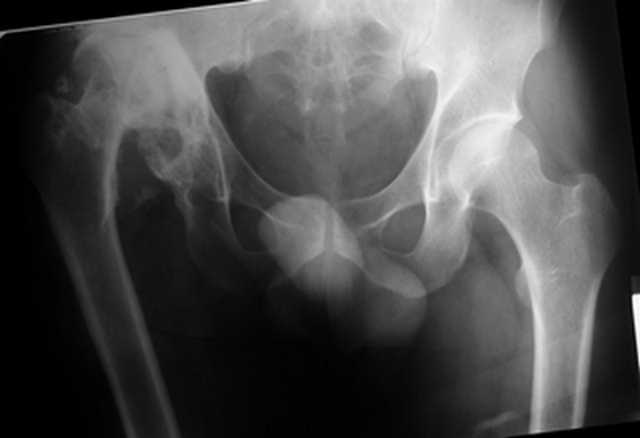

Пациент 30 лет 3 года назад в результате травмы получил травматический

дефект нижних конечностей до в/3 голеней, был пропущен вывих бедра. В настоящее время очень

неплохо ходит на протезах, движения в неоартрозе близки по объему к здоровой стороне.

Основная жалоба - выраженная боль при ходьбе. планируем двухэтапное эндопротезирование -

задним доступом мобилизовать проксимальный отдел бедра, резецировать шейку, аппаратом

низвести бедро(головку оставить там где она есть, так как больших дефектов не видно(может

пригодится в последующем?)). Вторым этапом бесцементное эндопротезирование. Насколько

такой вариант реалистичен? Доступ для второго этапа? Может быть, другие варианты?